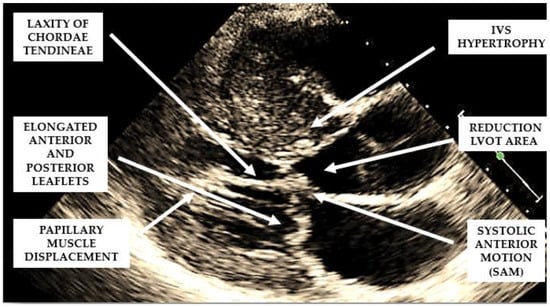

Several structural and functional abnormalities of the mitral valve may substantially contribute to LVOTO. The increase in length of the anterior and/or posterior mitral leaflets [10,11] (Figure 2), forward displacement of the anterior papillary muscle, and laxity of the mitral valve chords (Figure 2) have been implicated in the anterior displacement of the coaptation line and in abnormal leaflet coaptation, characterized by a posterior leaflet coapting the mid-portion of an anterior leaflet, leaving its distal portion unsupported. This part of the leaflet causes dynamic obstruction, via a combination of suction, caused by the Venturi effect of the rapid flow in LVOT, and a dragging mechanism, caused by blood pushing the leaflet towards the septum (Figure 2).

These dynamic changes result in mitral systolic anterior motion (SAM), which contributes to both LVOTO and mitral regurgitation. SAM is a common but non-specific finding in HCM. In fact, alternative causes of SAM, independently of the presence of LV hypertrophy, are hypovolemia, inotropic drug use, small ventricles in normal or hypertensive individuals, and mitral valve surgical repair.

When evaluating the presence and severity of obstruction in HCM, a systematic assessment of all the components of the mitral valve apparatus via 2D echocardiography is required. This technique allows a visualization of the presence and distribution of LV hypertrophy, the presence of SAM, elongation of mitral valve leaflets, displacement of papillary muscles, laxity of tendon cords and LVOT diameter reduction (Figure 2). In addition, 2D echocardiography allows a diagnosis of MCO via the observation of a typical hourglass appearance of the LV due to systolic septal contact with the anterolateral wall, which induces sphincter-like cavity obliteration, creating two distinct (basal and apical) LV chambers (Figure 5). In addition, 2D echocardiography allows a visualization of the presence of an apical aneurysm and any thrombotic formation. In this setting, contrast echo may also be helpful for the correct diagnosis.

Figure 2. Mechanisms involved in the generation of left ventricular outflow tract obstruction in patients with hypertrophic cardiomyopathy.